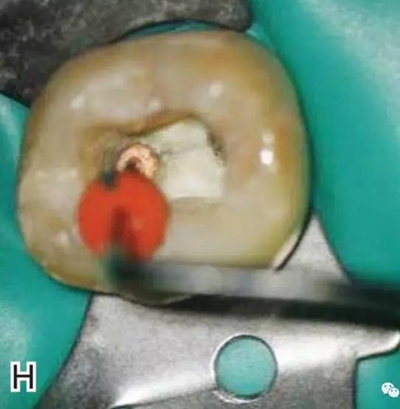

8、熱牙膠根中上段的充填

在完成根尖段的充填后,使用熱塑牙膠注射儀對根管中上段進(jìn)行分層充填,一般分2~3次完成充填,每次充填均使用相應(yīng)直徑大小的垂直加壓器進(jìn)行加壓。拍片確認(rèn)充填效果(圖8)。

圖8 熱牙膠根中上段的充填,A、B.注射儀注射中段熱牙膠

C、D.垂直加壓器加壓 E、F.注射儀繼續(xù)注射上段熱牙膠

G、H.垂直加壓器加壓 I、J.完成根中上段的充填